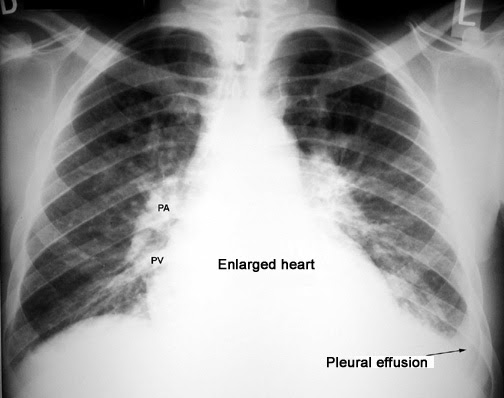

- Chest X-ray: This imaging test can reveal the presence of fluid in the pleural space, appearing as white areas on the X-ray film.

Chest X-ray. Pleural effusions appear white on X-rays, while air space looks black. If a pleural effusion is likely, you may get more X-ray films while you lie on your side. These can show if the fluid flows freely within the pleural space.

The image below shows a pleural effusion. (Click image to enlarge)